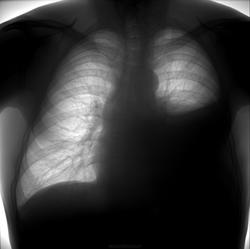

Левосторонний гидроторакс

Мужчина 46 лет, жалобы на нарастающую одышку в течении последних 3-4 месяцев

В транссудате обнаружены бластные клетки

Отсутствие выраженного смещения средостения в здоровую сторону при столь массивном выпоте предполагает либо фиксированное опухолью средостение, либо центрально расположенную опухоль.

В приведённом случае имело место незначительное смещение средостения вправо на первых снимках (правый контур сердца и правый корень сближены).

А вот отличить саму опухоль на фоне частично поджатого легкого мне не удалось, овальная тень на контрольном прямом снимке мне видится плевральными наложениями в переднем синусе. Возможно, изначально выпот был частично осумкованным, и видимая автору опухоль в язычковых сегментах - периферическая: мне не видно признаков центрального ателектаза слева любого объема, ни сегментарного, ни долевого. Малый гидропневмоторакс дренирован.

При оценке стоит обратить внимание, что левый корень расположен ниже обычного.

Корень слева на том же уровне, что справа, с учетом компенсаторного правостороннего грудного сколиоза. Смещения средостения вправо не произошло из-за спаек, которые после плевральной пункции стали хорошо видны. Они же осумковали ограниченный пневмоторакс. Узловая тень действительно очень похожа на периферический рак, но требует дифференцировки с осумкованным гидротораксом.  Томограммы будут? Предоставьте ФОГК за 2011 г., если есть возможность.